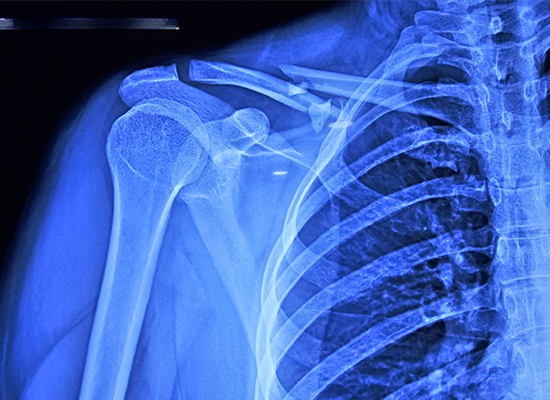

La patiente, une femme de 34 ans, a subi une fracture de la clavicule droite classée Allman type 1, ce qui signifie qu'il s'agissait d'une fracture de la diaphyse médiane. Ce type de blessure peut souvent entraîner des complications si elle n'est pas traitée correctement. Après avoir examiné l'état de la patiente et examiné ses résultats d'imagerie, le Dr Pedro a recommandé une procédure de réduction ouverte et de fixation interne (ORIF) avec une plaque de verrouillage de la clavicule S.

La patiente de 34 ans présentait une fracture de la diaphyse Allman de type I avec plusieurs fragments.

En raison de la nature multi-fragmentée et déplacée de la fracture, la fixation conservatrice n'a pas pu obtenir un alignement, c'est pourquoi ORIF a été sélectionné.